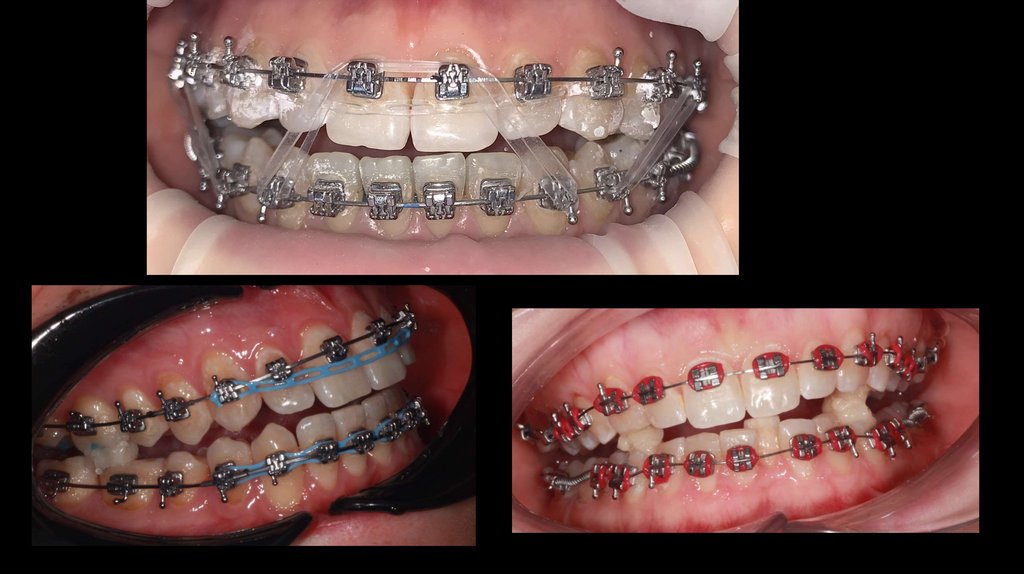

1ый План лечения.

Лечение на металлических брекетах

• Расширение верхней и нижней челюсти

• Нормализация положения отдельных зубов

• Нормализация прикуса во фронтальном отделе

27.

Брекеты – металлические

самолигируемые.

Фиксация по SAP.

Расширение верхней челюсти с помощью

широких дуг.

Обязательное ношение межчелюстных

эластиков.

Дезартикуляция (уже с помощью накладок)

Ортодонтические миниимплантаты

(минивинты) 3 – 4.